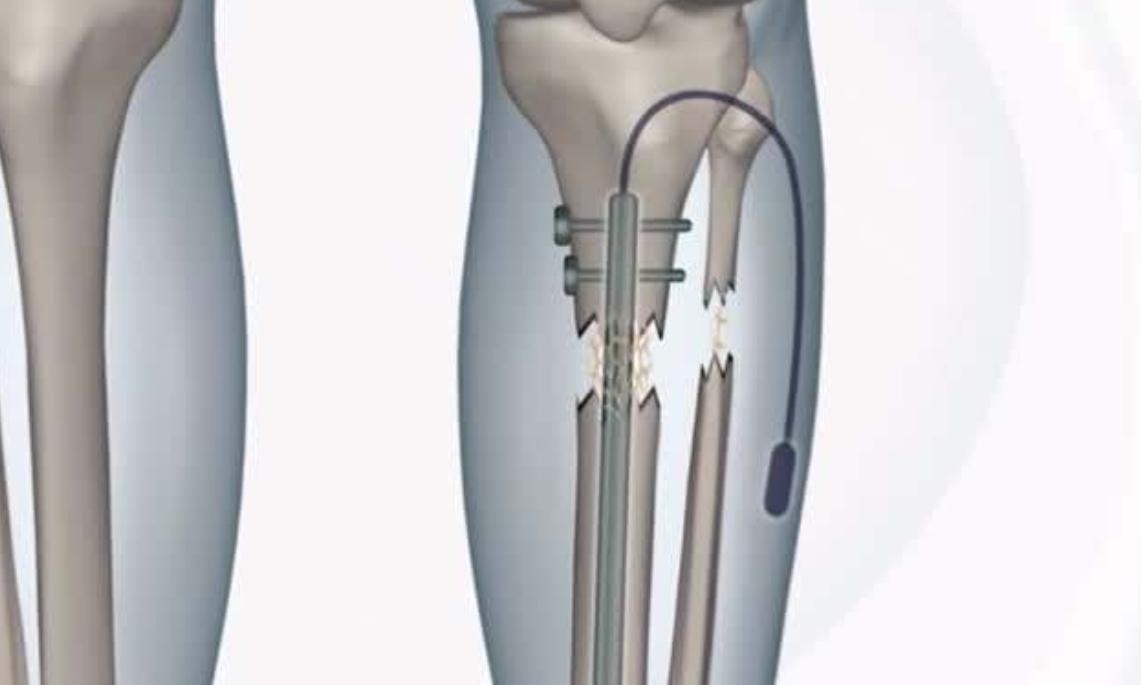

手术室中,医生为李亚诺进行了麻醉,然后就是长达六个小时的手术过程,切断双腿的骨头之后,医生用牵引器连接了大腿骨,这样之后可以每天保证骨头能够愈合一毫米,只要等骨头完全愈合之后再把牵引器取出就大功告成了。

原来,虽然成功的增高了7.2厘米,但是与此同时,“断骨增高”的后遗症也开始逐渐的显现出来,因为手术断骨的原因,李亚诺的肌肉、神经、血管都跟着一起拉长了,神经发生改变之后,导致了李亚诺根本无法正常行走。

除此之外,各种各样的“断骨增高”并发症也开始出现在他的身上,骨外翻、足弓塌陷等等症状都让李亚诺感到非常的痛苦,虽说身高得到了增长,但是李亚诺付出的代价却是原来正常的双腿。

骨头愈合之后,李亚诺已经无法再像以前正常时候一样行走,甚至最严重的时候都需要父母推着轮椅,他才能出门在外行动,简言之,就是李亚诺的双腿已经彻底的报废了。